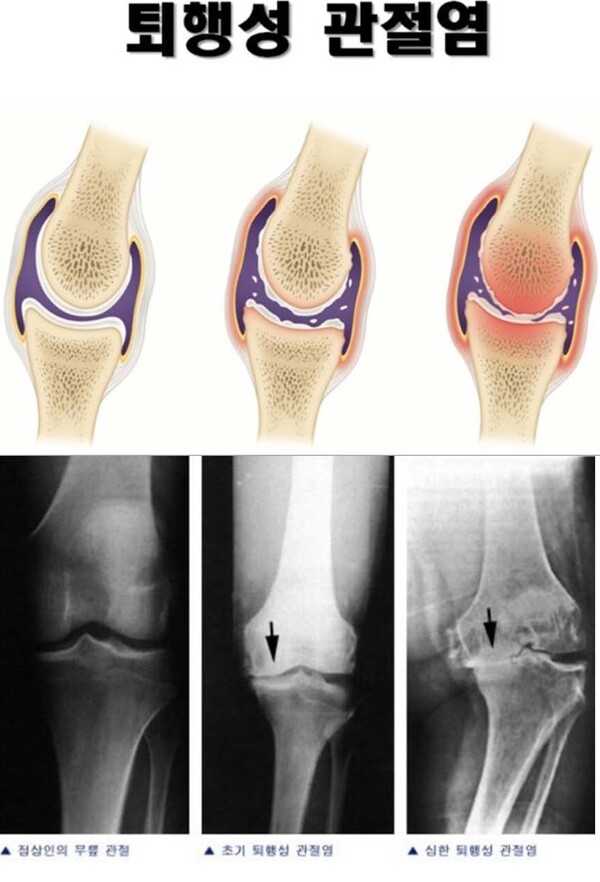

부산시 종합병원에서 근무하는 차모 간호사는 여성경제신문과 통화에서 "무릎을 굽혔다 폈다 하는 행위가 뼈와 뼈 사이 연골을 닳게 만들고 이는 퇴행성 관절염까지 이어질 수 있다"며 "무릎이 안 좋은 노인 분들에게 동양식 변기는 치명적일 수 있다"고 설명했다.

김보경 간호사도 "무릎이나 고관절 수술을 받으면 높은 변기를 사용하라고 권장할 정도로 (무릎이 좋지 않은 사람이) 쪼그려 앉는 행위는 피해야 한다"고 말했다.

경기도 소재 한 스포츠재활센터에서 운동치료사로 근무하는 박모 씨는 "쪼그려 앉아 변을 보는 행위는 무릎이 약한 노인 분들에게 치명적이다"며 "관절낭과 연골, 대퇴근육에 다 안 좋아 큰일난다"고 했다.